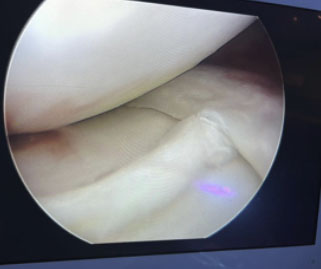

Rotura Meniscal en Asa de cubo